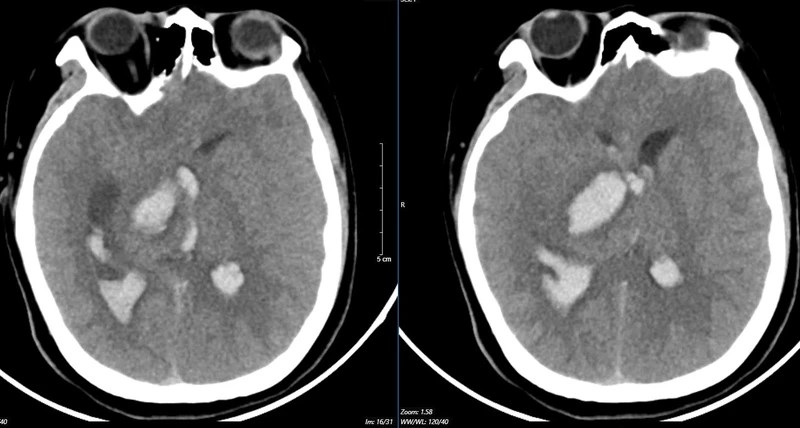

Kết quả chụp lại phim MSCT mạch não chảy máu não đồi thị - não thất do vỡ khối AVM của bệnh nhân 15 tuổi. |

Bệnh nhân 15 tuổi đến viện vì đột ngột đau đầu dữ dội. Bệnh nhi nhanh chóng rơi vào tình trạng hôn mê. Bệnh viện tuyến dưới tiếp nhận chẩn đoán bệnh nhi bị chảy máu não, lập tức được đặt ống nội khí quản thở máy và nhanh chóng chuyển ngay đến Bệnh viện Bạch Mai.

Bệnh nhân vào Trung tâm Đột quỵ, Bệnh viện Bạch Mai trong tình trạng hôn mê sâu, Glasgow 5 điểm, thở máy, giãn đồng tử bên phải. Kết quả chụp lại phim MSCT mạch não chảy máu não đồi thị - não thất do vỡ khối AVM (dị dạng thông động- tĩnh mạch não) biến chứng giãn não thất cấp, rối loạn thân nhiệt, sốt cao liên tục 39-40 độ C.